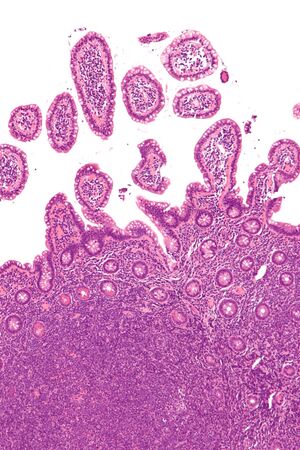

| صورة مجهرية mantle cell lymphoma، نوع من اللمفوما اللاهودجكينية. | |